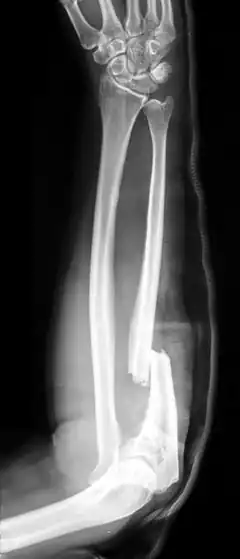

Abwehrverletzungen treten häufig an den Händen und Unterarmen auf, da diese Körperteile instinktiv zum Schutz eingesetzt werden. Zu den typischen Erscheinungsformen von Abwehrverletzungen zählen verschiedene Verletzungsarten an den Händen und Unterarmen. Stichverletzungen entstehen beispielsweise, wenn das Opfer versucht, das Messer des Angreifers zu greifen oder abzuwehren, was zu tiefen, schmalen Wunden führt. Schnittverletzungen treten auf, wenn das Opfer den Angriff abwehrt und dabei mit scharfen Gegenständen in Kontakt kommt, was längliche, oberflächliche Wunden zur Folge hat. Prellungen und Schürfwunden entstehen oft durch Schläge mit stumpfen Gegenständen oder durch das Abwehren eines Angriffs mit den Armen. Frakturen an den Knochen der Hände und Unterarme sind ebenfalls möglich, wenn das Opfer heftige Schläge abwehrt.